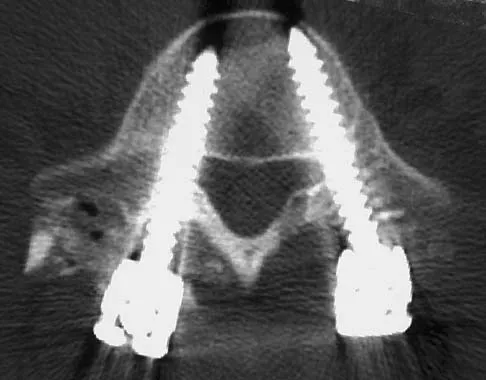

Figures 61a and 61b show the CT and MRI scans of a 40-year-old man who has hip pain. He undergoes total hip arthroplasty and curettage and cementation of the lesion as shown in Figure 61c. Histopathologic photomicrographs of the curettage specimen are shown in Figures 61d and 61e. What is the best course of treatment?

Explanation